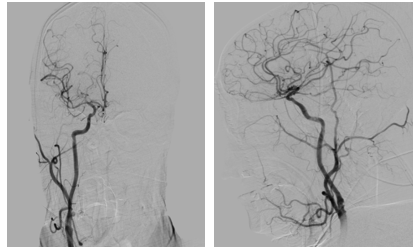

病历夹什么径技·第151期|串联营病历夹:京广连营_https://www.jmylbn.com_新闻资讯_第30张

病历夹什么径技·第151期|串联营病历夹:京广连营_https://www.jmylbn.com_新闻资讯_第31张

病历夹什么径技·第151期|串联营病历夹:京广连营_https://www.jmylbn.com_新闻资讯_第32张

病历夹什么径技·第151期|串联营病历夹:京广连营_https://www.jmylbn.com_新闻资讯_第33张

<<滑动查看下一张图片>>

• 术后即刻:去碘CT排除出血风险,梗死灶出现。

• 术后一天:DWI显示梗塞面积没有明显增大,MRA提示血管再通,发现存在LMCA动脉瘤。

• 术后四天:CT显示没有出血表现,梗死灶已经形成。

• 术后3个月:复查CT显示恢复情况良好。